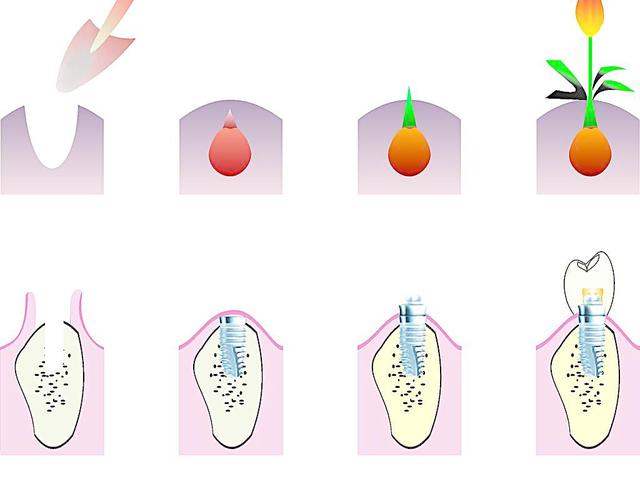

廊坊圣洁口腔医院的医师说,种植牙也叫人工种植牙,并不是真的种上自然牙齿,而是通过医学方式,将与人体骨质兼容性高的纯钛金属经过精密的设计,制造成类似牙根的圆柱体或其他形状,以外科小手术的方式植入缺牙区的牙槽骨内,经过1~3个月后,当人工牙根与牙槽骨密合后,再在人工牙根上制作烤瓷牙冠。 》》》相关阅读:廊坊市民种植牙成功的四要素